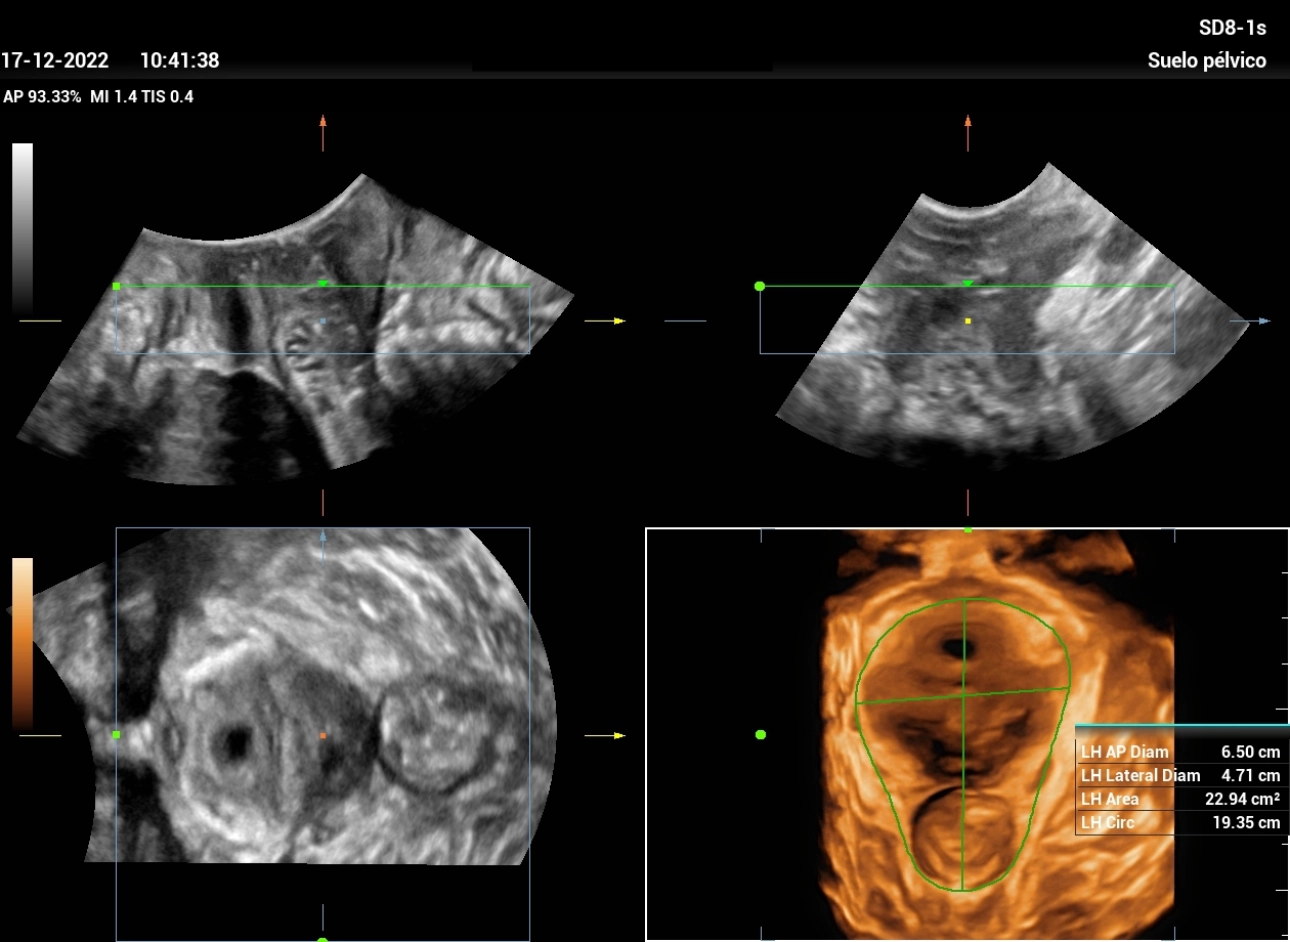

Ultrasound Journal 21 Ultrasound Evaluation of Stress Urine Stress Incontinence Ultrasound Stress urinary incontinence (sui), which refers to involuntary urine leakage due to physical exertion, sneezing or coughing, is the most common type. It helps in differentiating the various. Some people will still have urine. A test that measures the detrusor muscle pressure at rest and during activities like coughing and passing urine. Treatments for stress incontinence often can greatly reduce,. Stress Incontinence Ultrasound.

Ultrasound Journal 21 Ultrasound Evaluation of Stress Urine Stress Incontinence Ultrasound The minimum evaluation before primary midurethral sling surgery in women with symptoms of sui includes the following six. Stress urinary incontinence (sui), which refers to involuntary urine leakage due to physical exertion, sneezing or coughing, is the most common type. Stress urinary incontinence (sui) is the involuntary, sudden loss of urine secondary to increased intraabdominal pressure that is bothersome or. Stress Incontinence Ultrasound.

Ultrasound Journal 21 Ultrasound Evaluation of Stress Urine Stress Incontinence Ultrasound A test that measures the detrusor muscle pressure at rest and during activities like coughing and passing urine. Treatments for stress incontinence often can greatly reduce, and possibly stop, urine leakage. It helps in differentiating the various. Stress urinary incontinence (sui) is the involuntary, sudden loss of urine secondary to increased intraabdominal pressure that is bothersome or affecting the. Some. Stress Incontinence Ultrasound.